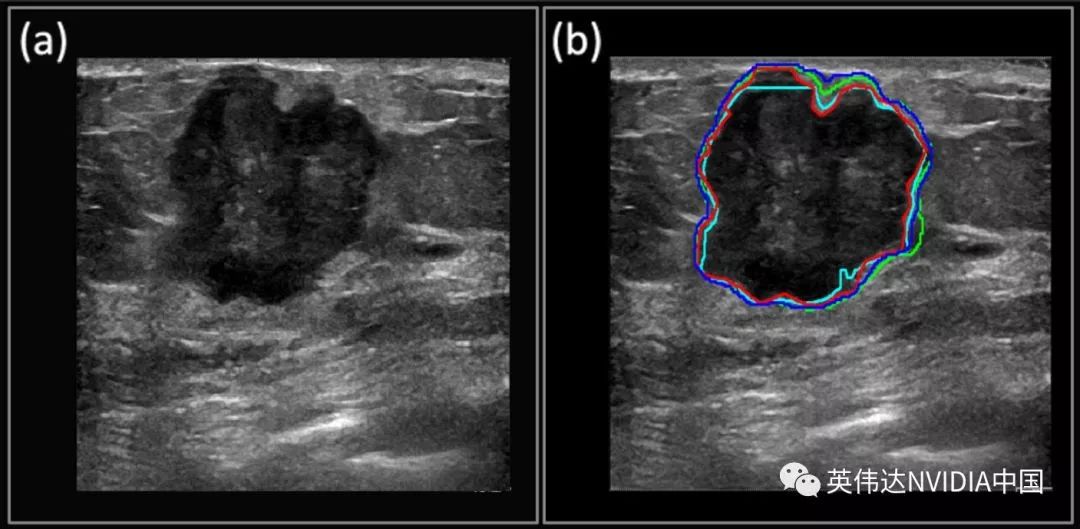

Mayo诊所的研究人员Viksit Kumar正在领导一项工作,利用GPU支持的推理技术,通过超声波设备更准确地对乳腺癌图像进行分类,这种设备在全世界范围内都更便宜,也更容易获得。

根据他们的研究论文,Kumar和他的团队已经能够非常准确地检测和分割乳腺癌肿块,很少出现假阳性。

红色轮廓显示了人工分割的肿瘤边界,而深度学习预测的边界以蓝色、绿色和青色显示。

该团队使用NGC注册表中的TensorFlow深度学习框架容器在NVIDIA GPU上进行本地处理。它还使用NVIDIA V100 Tensor核心GPU在AWS上使用相同的容器。

最终,Kumar希望将超声波图像用于其他类型疾病的早期检测,如甲状腺癌和卵巢癌。